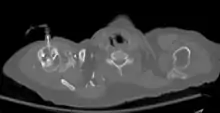

The tibia IO insertion site is just below the medial condyle, labeled in this picture. | |

The needle is inserted through the bone's hard cortex and into the soft marrow interior, which allows immediate access to the vascular system. The IO needle is positioned at a 90 degree angle to the injection site, and is advanced through manual traction, impact driven force, or power driven. Each IO device has different designated insertion locations. The most common site of insertion is the antero-medial aspect of the upper, proximal tibia as this site lies just under the skin and is easily located. Other insertion sites include the anterior aspect of the femur, the superior iliac crest, proximal humerus, proximal tibia, distal tibia and the sternum (manubrium).[1] Although intravascular access is still the preferred method for medication delivery in the prehospital area, IO access for adults has become more common. As of 2010, the American Heart Association no longer recommends using the endotracheal tube (ET) for resuscitation drugs, except as a last resort when IV or IO access cannot be gained.[1] ET absorption of medications is poor, and optimal ET drug dosings are unknown. IO administration is becoming more common in civilian and military pre-hospital emergency medical services (EMS) systems globally.[11]